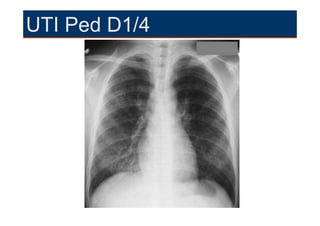

UTI Ped D1/4